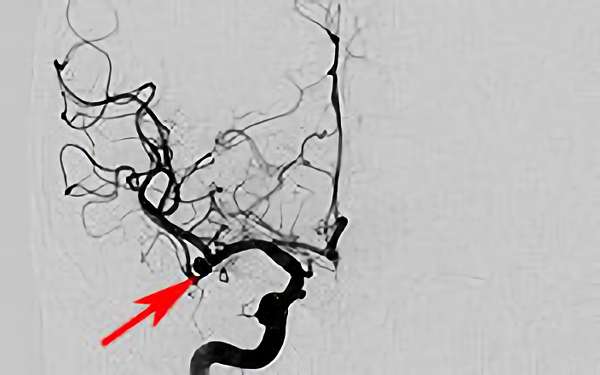

前交通動脈瘤

No.1627 手術前